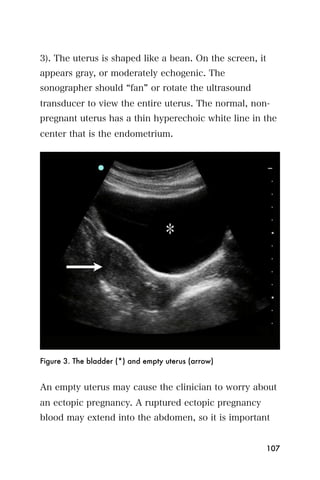

3). The uterus is shaped like a bean. On the screen, it

appears gray, or moderately echogenic. The